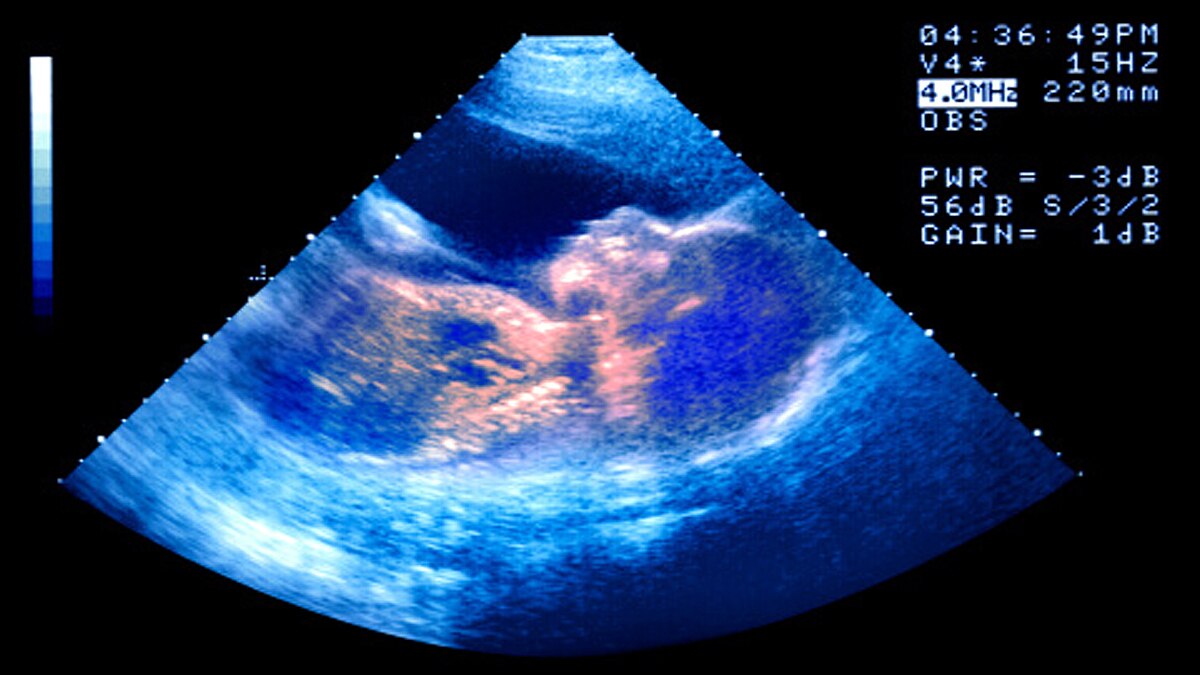

नाद्जा रीसलैंड ने बच्चे के चेहरे की भावभंगिमाओं का अध्ययन किया. उनके मूवमेंट की 4डी अल्ट्रासाउंड इमेजिंग की. साथ ही 3डी फिल्म बनाई. ताकि चेहरे पर होने वाले बदलावों को देखा जा सके. इस स्टडी में उन्हें दिखाई दिया कि बच्चे गर्भ के अंदर रोने जैसे एक्सप्रेशन देते हैं. जिसे क्राई-फेस-जेस्टाल्ट (Cry-Face-Gestalt) और लॉफ्टर जेस्टाल्ट (Laughter Gestalt) कहते हैं. आमतौर पर चेहरे के ये भाव 24 से 35 हफ्तों में आने शुरु होते हैं. (फोटोः गेटी)